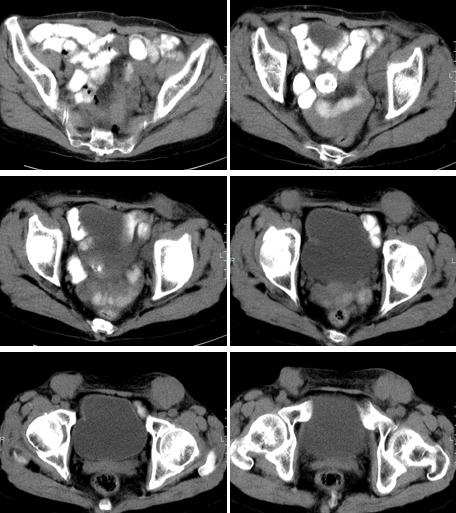

女,65岁,三月前发现腹部包快,无临床症状。

淋巴瘤(两腹股沟及左髂窝).前腹皮下转移.

因为没有强化扫描和详细的临床情况{如肿块是否有移动,按压痛}对肿块是否是淋巴结组织或实性组织的判断带来困难。病灶位于腹白线和腹股沟旁{而且是对称分布!},首先应该考虑是淋巴结,至于是何种原因引起的淋巴结肿大只能结合临床考虑。另外要考虑到3楼战友分析的硬纤维瘤{属于良性},还有腹壁续发性肿瘤它也具有沿淋巴转移的特点。

腹股沟淋巴结对称增大,考虑腹壁的纤维瘤.

腹壁皮下脂肪内及双侧腹股沟区多发软组织密度肿块,肿块形态不规则,与皮肤粘连,根据其多发的特点,结合患者为老年女性,三月前新发病灶,应该首先考虑为转移性病变,应积极寻找原发癌瘤。

双侧腹股沟见肿大淋巴结,下腹部前壁类圆形等密度影,不除外转移性病灶,支持21楼分析。

前腹壁皮下及两侧腹股沟多发结节,境界清晰,周围脂肪间隙清晰,考虑良性病变,硬纤维瘤。